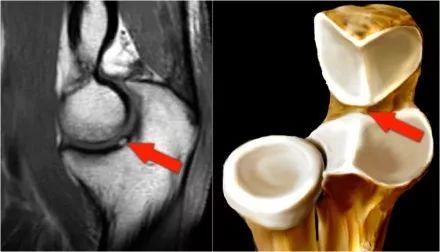

然后在肱骨小头孔钻和用自体骨和软骨填充缺陷。,在这里,在肱骨小头的孔填充有四块骨头和软骨。肱骨小头的对侧是桡骨头。